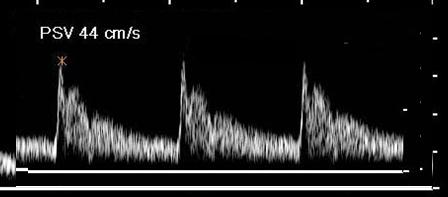

Where is the waveform?

vertebral